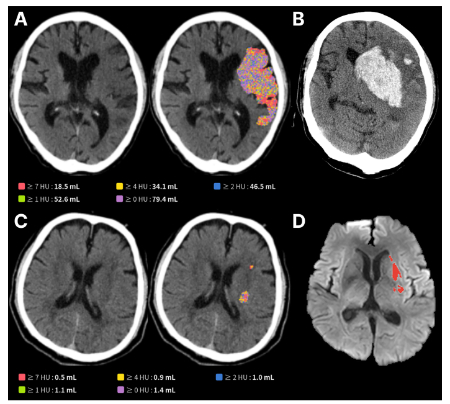

이 발표에서 김 대표는 제이엘케이의 뇌졸중 AI 영상 분석 솔루션이 실제 임상 환경에서 어떻게 활용되고 있는지에 관해 설명하는 동시에 진단 정확도 향상, 치료 결정 시간 단축, 진단 워크플로우 개선 등에 AI 기술이 어떤 기여를 하는지를 다기관 연구와 임상 논문 결과로 제시할 예정이다.